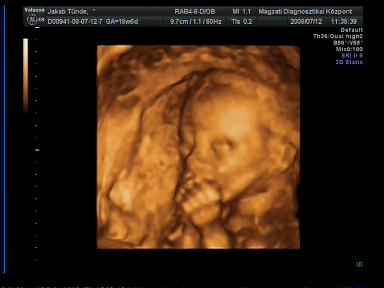

Jók a pocifotók!

Szeretnék segítséget kérni fizetős genetikai UH ügyben: ki hol járt és mennyire volt megelégedve a szolgáltatással? Ja, és a legfontosabb, hányadik hétig lehet menni ilyen genetikai UH-ra???

Ugyanis ma voltam a kórházban UH-n és kb. 3 perc alatt lerendeztek. A doki közlékeny volt, de nagyon rohamtempóban történt minden. Szóval hogy megnyugodjak teljesen, szeretnék elmenni egy alaposabb vizsgálatra is. A nemének beazonosításában is nagyon készséges volt doki bácsi, de Pötty szégyenlős volt (lehet, ez már utal valamire

) és jól összezárta a lábait. Amúgy az ő vizsgálatuk szerint minden ok. És medence végű, ami nem tudom, hogy jót jelent-e, mindenesetre a doki ezzel magyarázta, hogy nem tud sokat mocorogni, mert nincs túl sok helye ott.